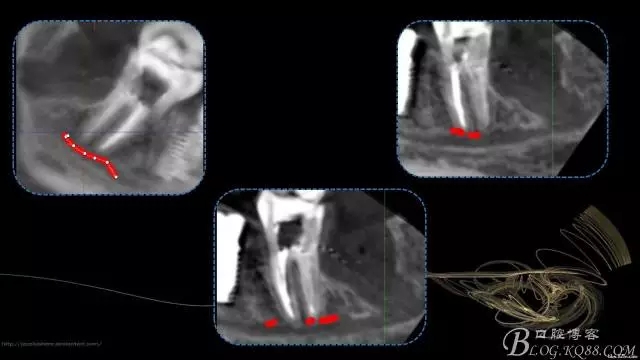

行走在神經(jīng)管上的根管治療